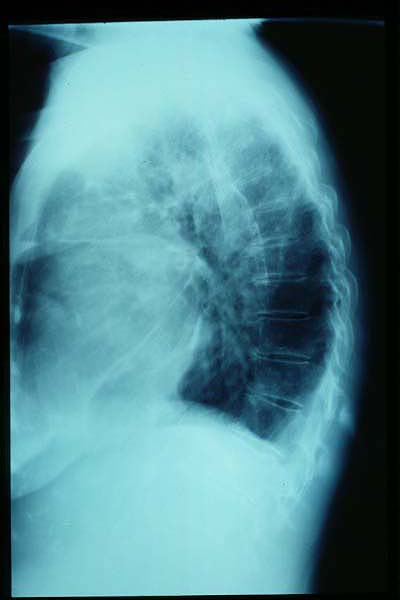

Osteoporosis. Cifosis.